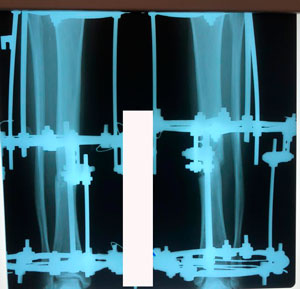

в процессе работы

перед фиксацией